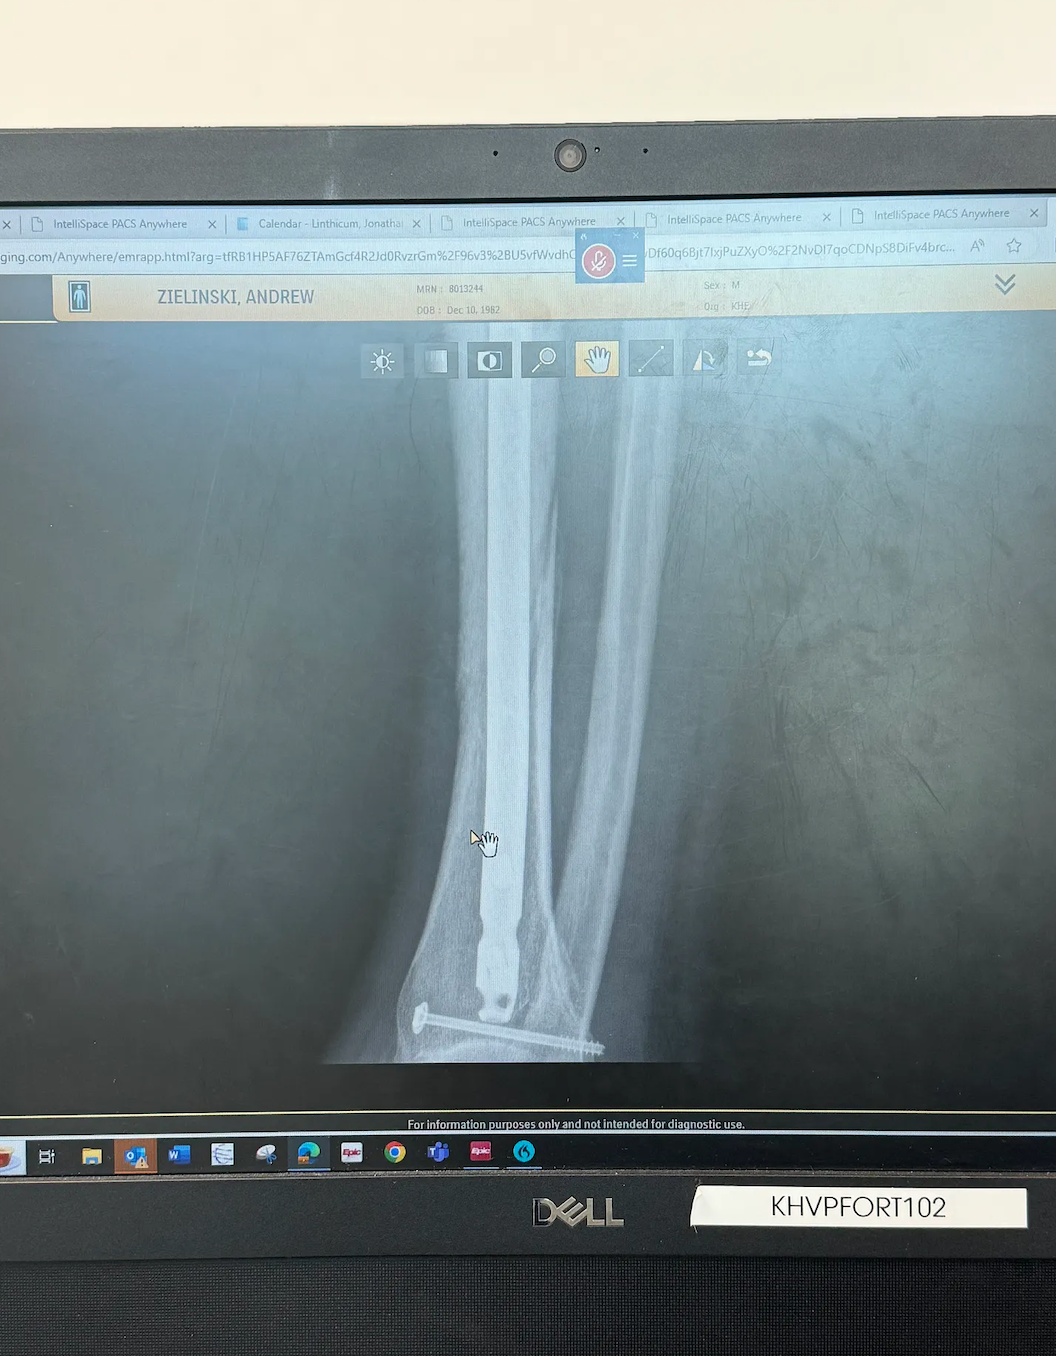

The x-ray at 6 weeks came back super positive. Majority of the break has come back together. I am cleared for about 25lbs of pressure. If you want to know what that is, simply pull out our scale, put your foot on the scale until you see 25lbs. In the comments below, tell me what your initial thought of what that feels like is!